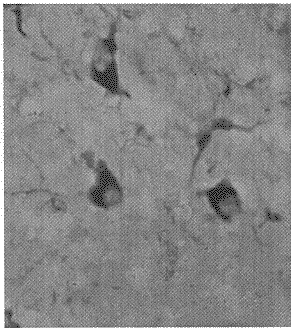

2.4 黑质NADPH阳性细胞的变化 大鼠纹状体注射6-OHDA 4周后,受损侧黑质区较未损侧出现增多的NADPH阳性胶质样细胞(图3~5)。

图3 帕金森病大鼠模型未损侧黑质区NADPH阳性胶质样细胞×200

Figure 3 NADPH-diaphorase positive glia cell in the substanstia nigra of unlesioned side in rat model of PD

图4 帕金森病大鼠模型受损侧黑质区NADPH阳性胶质样细胞×200

Figure 4 NADPH-diaphorase positive glia cell in the substanstia nigra of lesioned side in rat model of PD

图5 帕金森病大鼠模型受损侧黑质区NADPH阳性胶质样细胞 ×400

Figure 5 NADPH-diaphorase positive glia cell in the substanstia nigra of lesioned side in rat model of PD